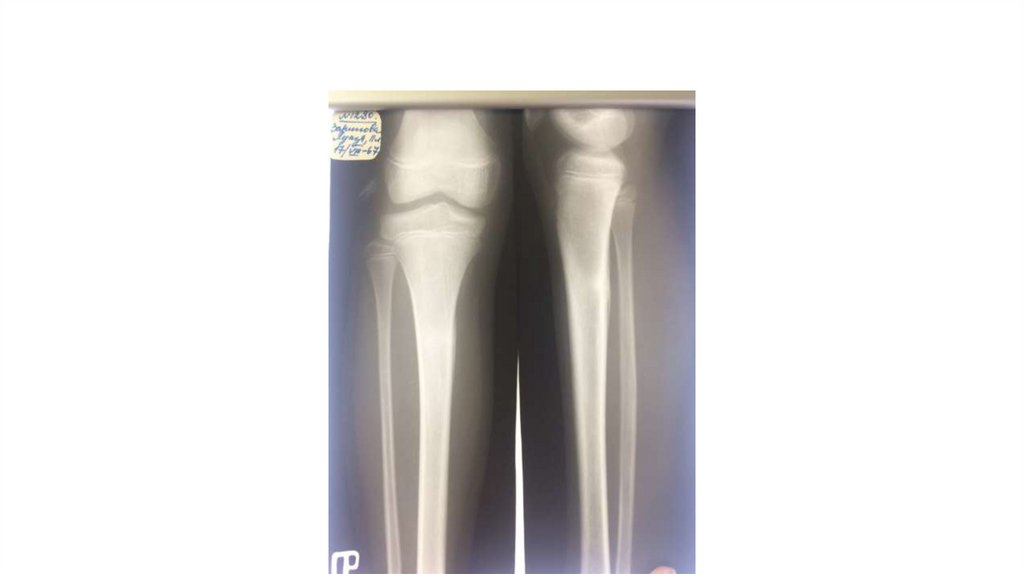

Воспалительные заболевания опорнодвигательного аппарата

«Воспалительные

заболевания опорнодвигательного аппарата»